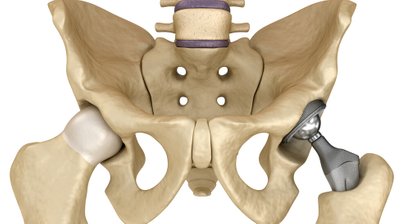

Hüftprothese

Ist die Hüfte durch degenerative Veränderungen (fortgeschrittene Hüftarthrose) oder traumatisch bedingt stark verschlissen bzw. geschädigt und lassen sich eine ausreichende Linderung der Beschwerden und der gewünschte Behandlungserfolg mit konservativen oder gelenkerhaltenden chirurgischen Maßnahmen...